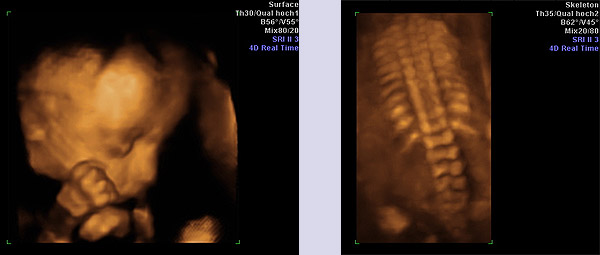

Die Möglichkeit, Ultraschallaufnahmen dreidimensional zu speichern, wird als 3D Technik bezeichnet. Dank sehr schneller Verrechnung dieser Bilder ist es möglich diese Bilder annähernd in Echtzeit wiederzugeben. Dann spricht man von 4D- Aufnahmen. Dieses Werkzeug nutzt der Pränataldiagnostiker, um Organe genauer untersuchen zu können (z. B. Gehirn). Wie bei einer Kernspinnuntersuchung können dreidimensionale Volumenblöcke gespeichert werden, die dann in der Nachschau beliebig gedreht und geschnitten werden können. In der Hand des Geübten ein großer diagnostischer Gewinn. Natürlich können auch Oberflächen (z.B. Gesicht) betrachtet werden, dies stellt jedoch nur einen kleinen Anteil an Möglichkeiten der 3D Technik dar.

Ca. 1% aller Kinder kommen mit einem Herzfehler zur Welt. Beim Ungeborenen werden die meisten Herzfehler nicht kreislaufwirksam, erst in den ersten 48h nach der Geburt kann es zu einem kritischen Zustand des Kindes kommen. Deshalb sollten die schweren Herzfehler vor der Geburt erkannt werden und so eine optimale Versorgung der Babys schon vorgeburtlich planen zu können. Die Erkennung solcher Herzfehler ist der fetalen Echokardiographie vorbehalten. Bei dieser sehr eingehenden Untersuchung des fetalen Herzens werden ca. 85% der schweren Herzfehler erkannt. Dies bedarf einer speziellen Ausbildung und die Erlaubnis muss durch eine entsprechende Prüfung erworben werden.